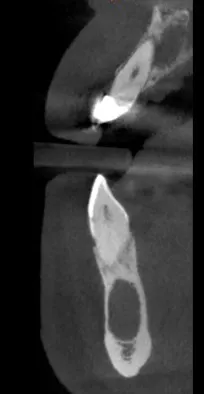

Another example is the new emergency patient who presents to your practice with severe pain. He or she had been telling the previous dental provider several days or weeks earlier that a particular tooth was causing discomfort; however, the dental provider saw no indications of tooth decay, infection, fracture, missed endodontically treated canals, or pathosis (figure 2) since he or she did not have a CBCT system. But, since you have the right tool for the job, you can zero in on the cause of pain and address it immediately.

Figure 2: Upper periapical lesion, lower possible odontogenic keratocyst